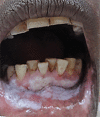

Tooth staining. These extrinsic stains are due to long term betel quid with tobacco use.